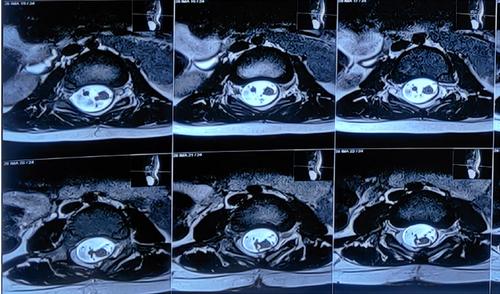

脊柱MRI显示硬膜内结节状病变(图2)在L2水平脊髓栓系的椎管后部,脊髓纵裂的特征(图3)和L4-5水平的背侧真皮窦,有脊髓栓系。CT扫描(图4)显示在L2、L3、L4、L5的后弓中的缺陷,以及在椎管、椎骨中的所有骶骨溶胶,在右侧L4/5小关节中注意到的部分融合,以及在椎管和L4/5水平的皮肤之间注意到的细的线性纤维化样束,可能是真皮窦。对颅脊髓轴进行筛查以排除脑积水和Arnold-Chiari畸形。根据临床和放射学表现,患者被安排手术。手术通过背部腰部区域的中线皮肤切口进行。暴露后,被证实为I型脊髓分裂畸形(SCM),硬膜外骨刺位于D12-L2椎骨水平。每个半索都有自己的硬膜囊和独立的脂肪脊髓脊膜膨出。使用高速钻在硬膜外显微镜下切除骨刺。硬脑膜以倒置的Y形方式打开。通过使用细致的显微神经外科解剖,对白线(脂肪瘤组织和脐带组织之间的界面)进行脂肪瘤组织的切除和脐带的解开。患者接受了脊髓松解术,同时切除了髓外硬膜内皮样肿块和脂肪瘤(图5和6)。术中模拟对肛周括约肌和下肢肌肉没有产生显著的反应。该患者接受了术中体感和运动诱发电位神经监测,未发现诱发电位间歇性降低。肿块的病理显示皮样囊性病变。

图3、MRI脊柱轴位图显示脊髓纵裂,其特征是脊髓在D12水平以下纵向分裂成两个半索